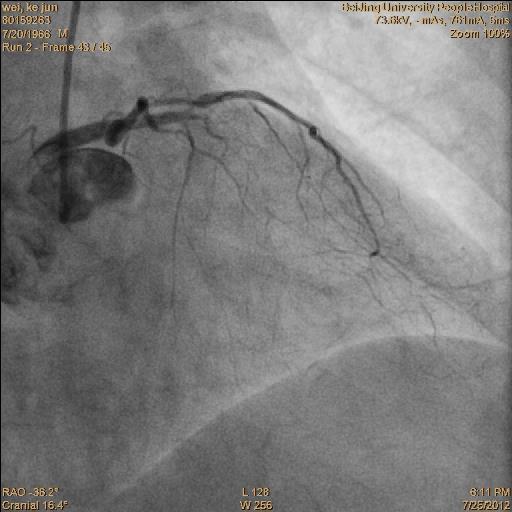

冠脉造影提示:双支病变。 见下图:

•术后一周复查造影,了解LIMA桥的状况,同时行RCA 和D的介入治疗。见下图: